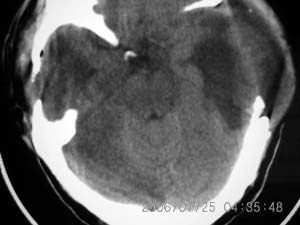

以下是引用lushijun在2006-7-25 21:02:00的发言:[br]1、双侧枕叶脑挫裂伤 2、硬膜下血肿 3、蛛网膜下腔出血[br]

以下是引用同在2006-7-25 21:11:00的发言:[br]双侧枕叶脑挫裂伤 硬膜下血肿 蛛网膜下腔出血

以下是引用kbzyycm在2006-7-25 22:54:00的发言:[br]1、双侧枕叶脑挫裂伤 、硬膜下血肿 蛛网膜下腔出血.[br]